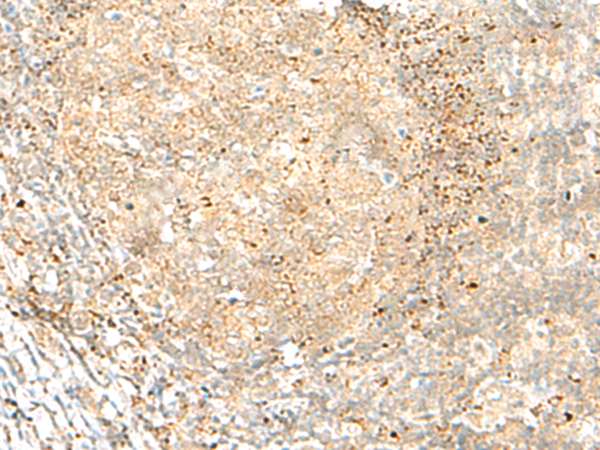

分类: 科研抗体货号: P13579别名: HLA-DR1B; HLA-DR3B应用: WB,IHC反应种属: Human